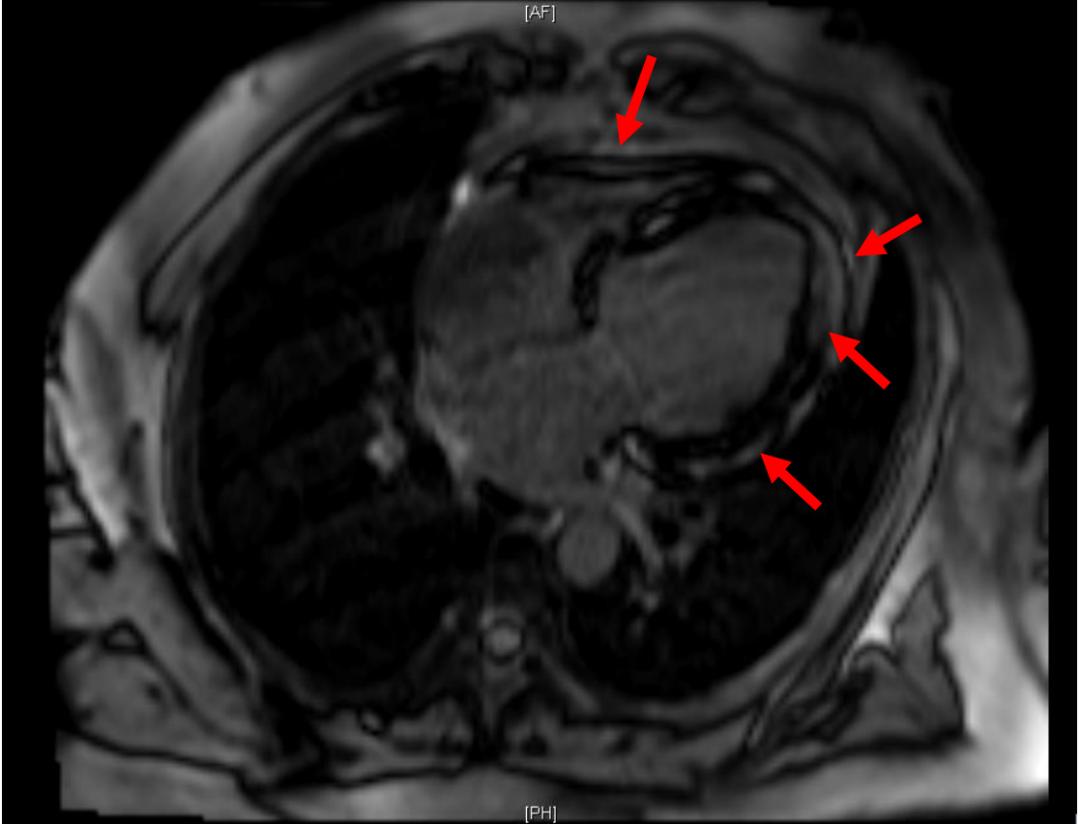

D:磁共振成像:心脏体积增大,以心房为著 , 左心室心肌壁增厚

4°:磁共振: 延迟强化示 左室心肌弥漫性条片状延迟强化影 ,大部分病灶位于心肌中层,前壁及间隔壁为著。